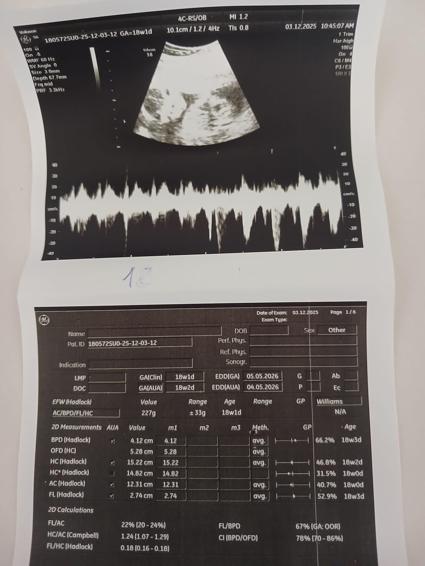

Hastada herhangi bir nörolojik kayıp oluşmadığı bildirildi. Ameliyat sonrası süreçte anne ve bebeğin sağlık durumlarının iyi olduğu, bebeğin gelişiminin normal seyrettiği belirtildi. Şu an 23'üncü haftasında olan Aydoğan'ın bebeğinin cinsiyetinin erkek olduğu öğrenildi.

Ameliyata giren Medicana Zincirlikuyu Hastanesi Kadın Hastalıkları ve Doğum Uzmanı Doç. Dr. Suat Süphan Erşahin de “Hastanın gebeliği vardı. Büyük bir cerrahi girişim planlanıyordu. Gebelik eşliğinde yapılan bu tür büyük operasyonlarda hem operasyon öncesinde hem de sonrasında bebeği mutlaka detaylı şekilde değerlendiriyoruz. Çünkü bu süreçte hem hasta hem de cerrah doğal olarak tedirgin olabiliyor. Biz hem preoperatif hem de postoperatif dönemde bebeğin gelişimini, kalp atışlarını ve genel durumunu yakından takip ettik. Amniyon muayeneleri dahil tüm kontrolleri yaptık ve her şeyin normal olduğunu gördük. Operasyon başarıyla tamamlandıktan sonra bebeği tekrar inceledik. Hem anneye gösterdik hem de onun bu süreci güven ve mutlulukla atlatmasını sağladık. Bizim için her büyük cerrahi girişimde, özellikle gebelik varsa, operasyon öncesi ve sonrası değerlendirme olmazsa olmazdır" ifadelerini kullandı.